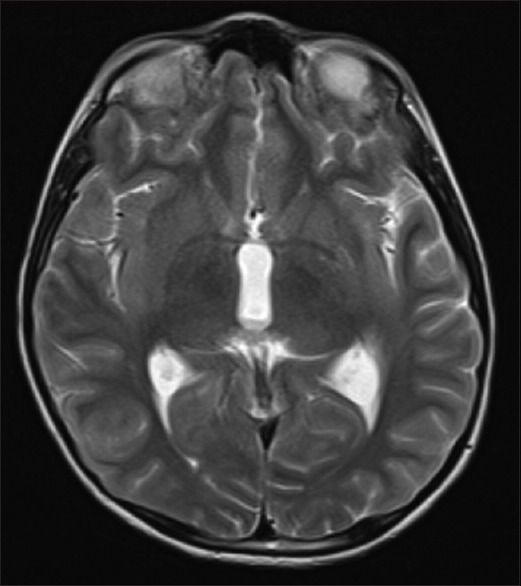

原发性弥漫性脑膜原始神经外胚层肿瘤是一种罕见的脑膜肿瘤,可伪装成慢性脑膜炎。虽然临床表现和放射学特征可为这种疾病提供线索,但脑膜活检是确诊的关键。在这种情况下,对经验性治疗无效的神经感染病例进行重新评估时,必须保持高度的怀疑和较低的门槛。我们介绍了一个 9 岁男孩的病例,他因慢性脑膜炎伴脑积水开始接受抗结核治疗。脑膜活检显示他患有原发性弥漫性脑膜原始神经外胚层肿瘤。

Primary diffuse leptomeningeal primitive neuroectodermal tumor is a rare meningeal neoplasm which can masquerade as chronic meningitis. While the clinical presentation and radiological features may provide a clue to this condition, meningeal biopsy is essential to clinch the diagnosis. A high index of suspicion and a low threshold for re-evaluating cases of neuroinfection that do not respond to empirical therapy are essential in this scenario. We present the case of a nine year old boy who was initiated on antituberculous treatment for chronic meningitis with hydrocephalus. Meningeal biopsy revealed a primary diffuse leptomeningeal primitive neuroectodermal tumor.